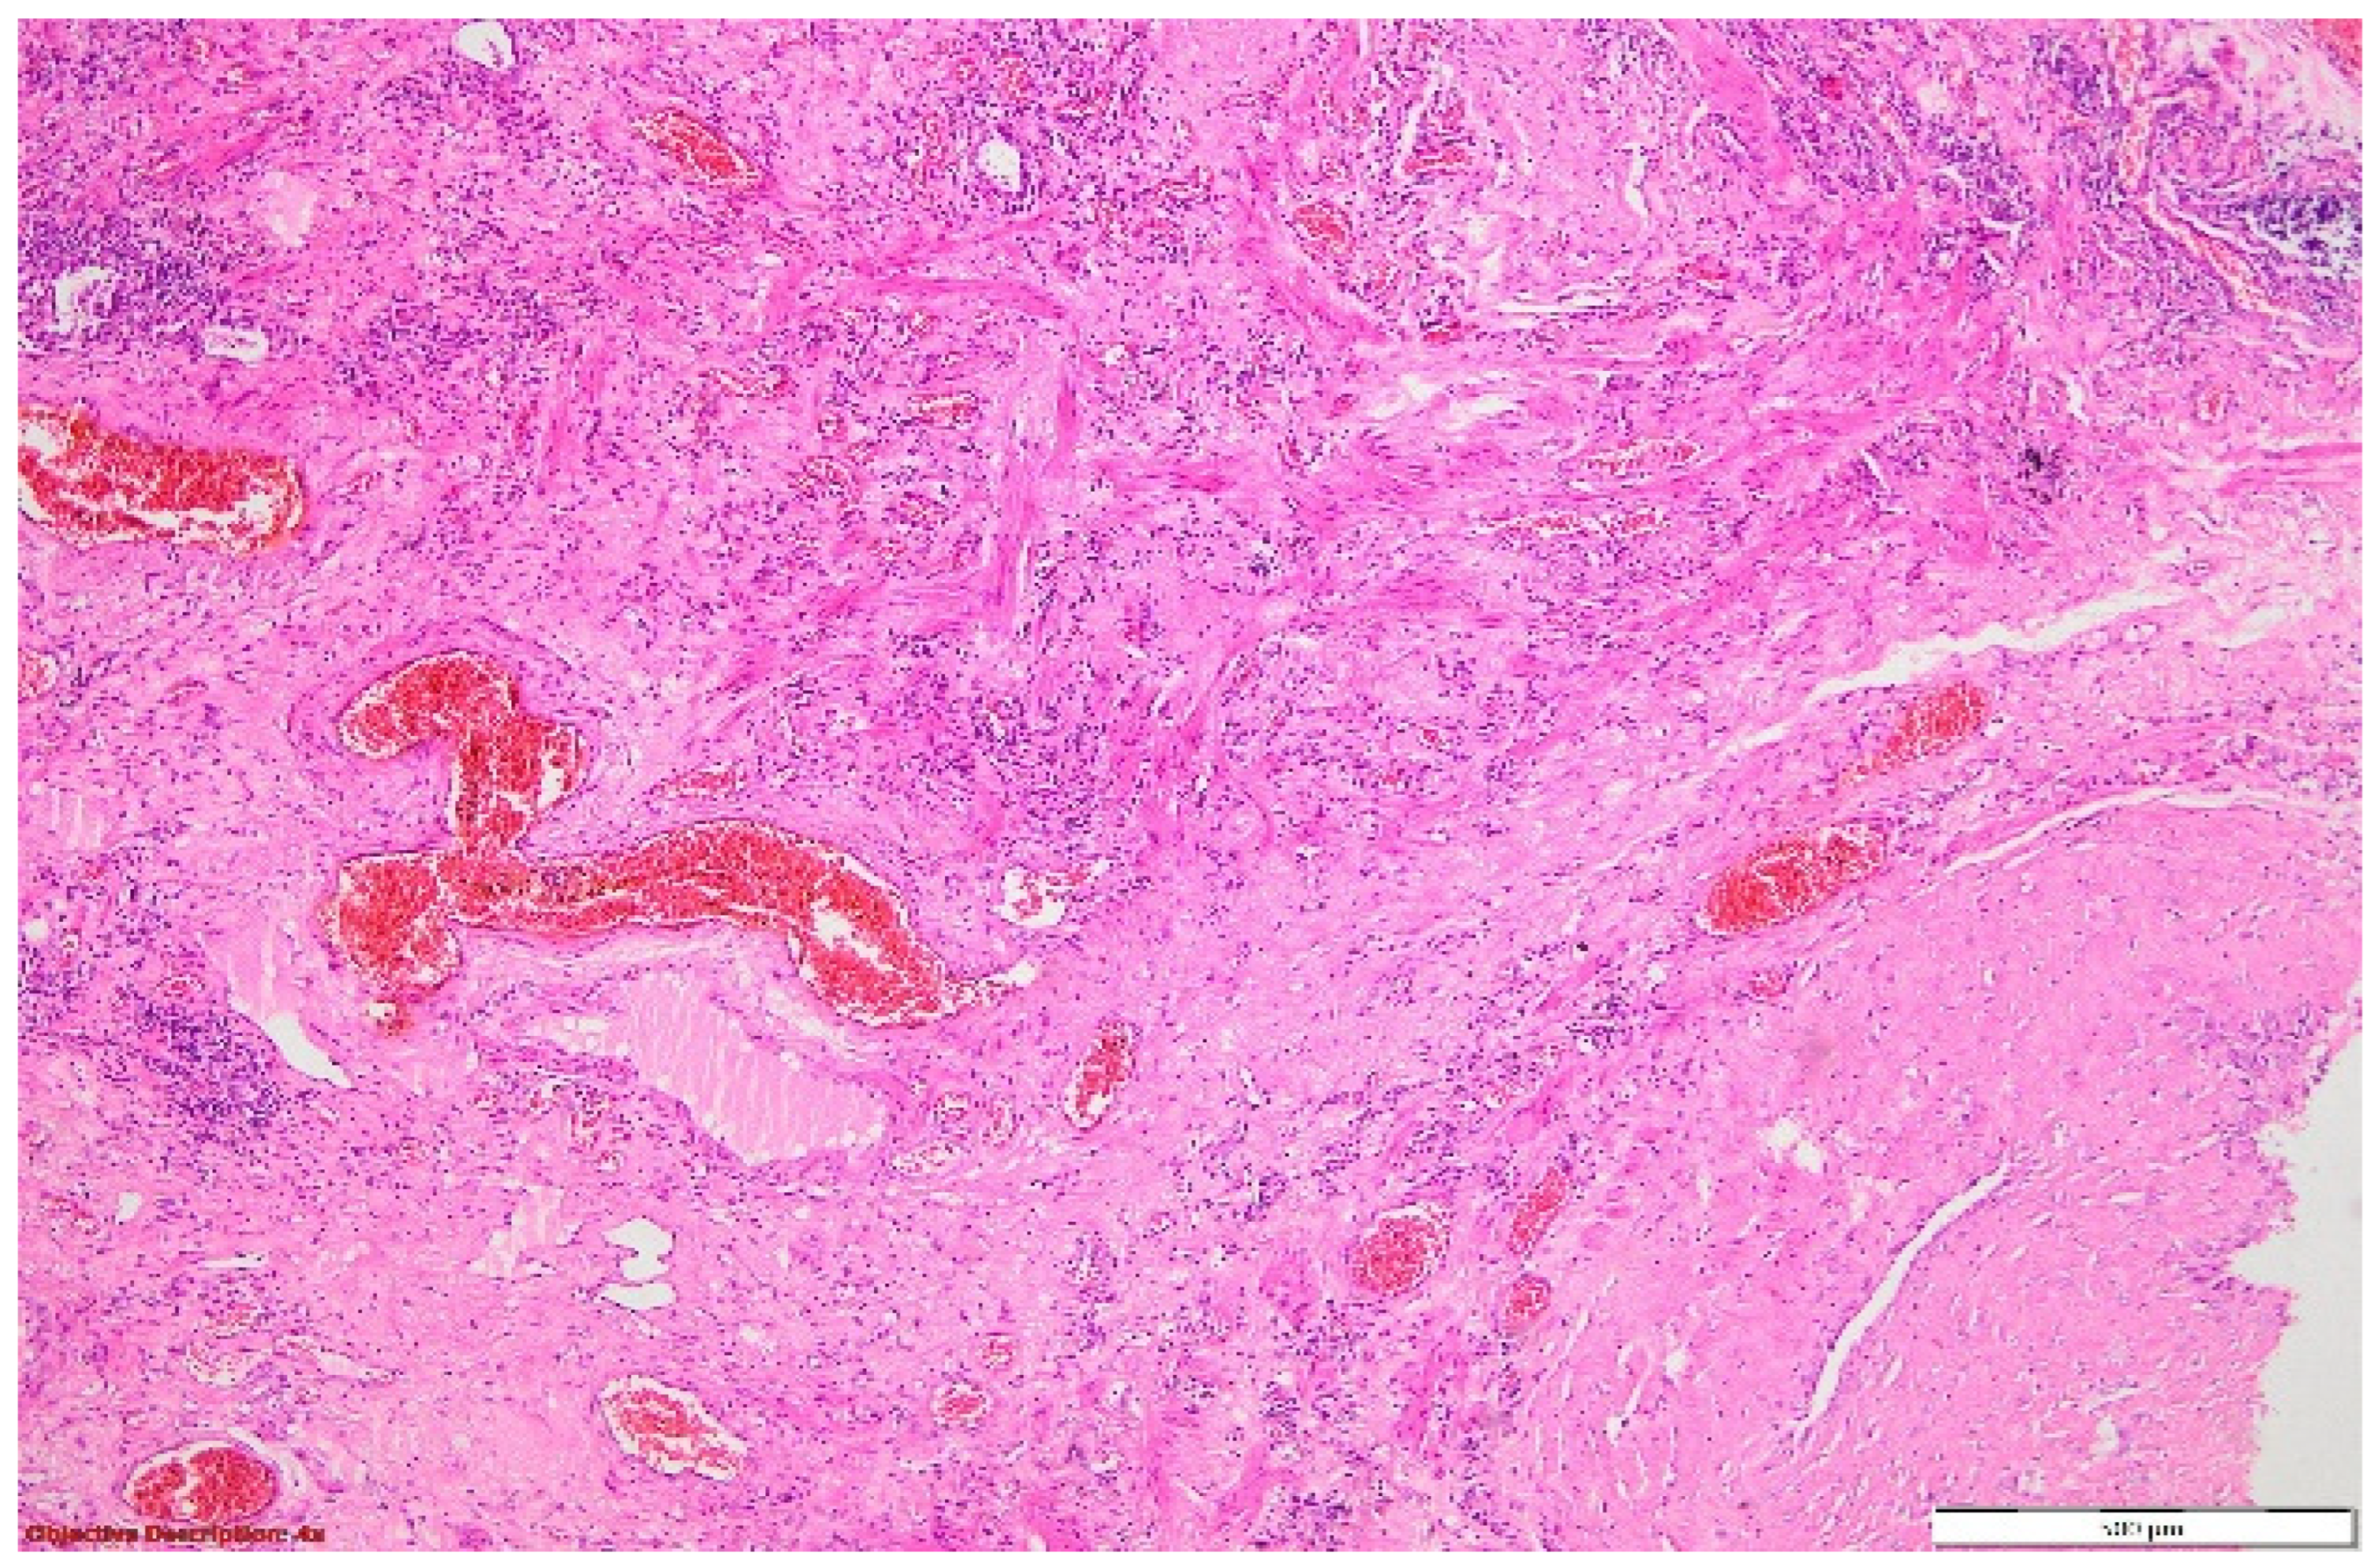

Figure 10. Significant smooth muscle proliferation in the pulmonary parenchyma was visible in the blood vessel’s tunica media and interstitial space. HE, 40×.